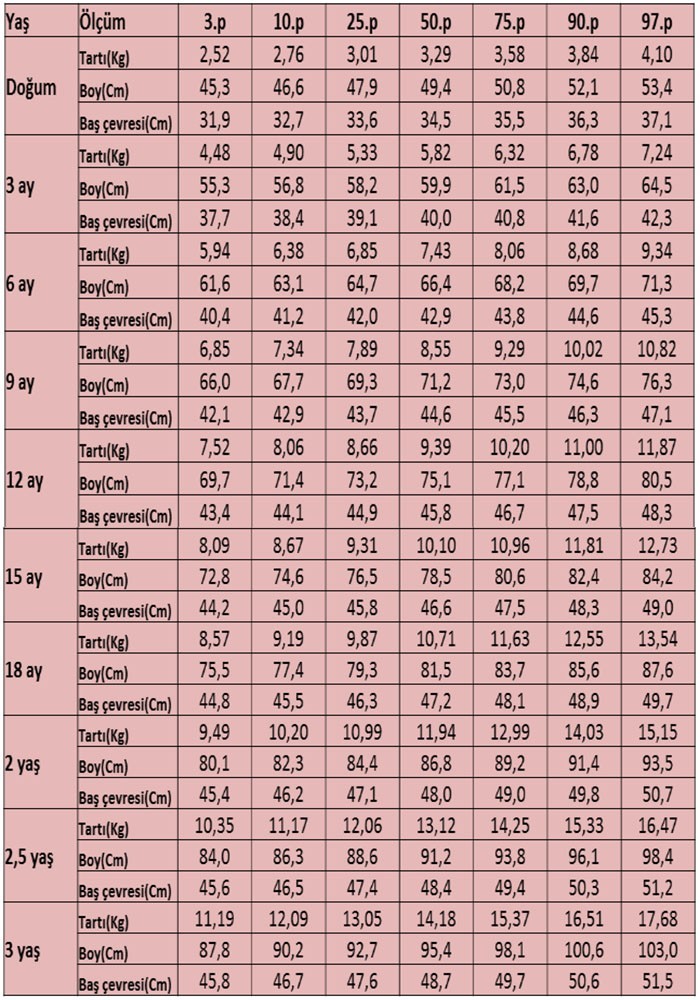

Ortalama 8 aylık bir kız bebeğin 8.000 gram civarında bir kiloya sahip olacağı, yapılan araştırmalar ve alınan ortalamalar ile belirlenmiştir.

Ortalama 8 aylık bir kız bebeğin 8.000 gram civarında bir kiloya sahip olacağı, yapılan araştırmalar ve alınan ortalamalar ile belirlenmiştir. 10 aylık kız ortalamada 71,5 cm uzunluğundadır. Acıbadem maslak hastanesi riskli gebelikler uzmanı doç. Gebelikte hafta hafta bebeğin kilosu ve boyunu hesaplama. 3 aylık erkeklerin ise ortalamada 6,4 kg olması beklenmektedir. Trimesterde i̇htiyacın olacak 6 şey, anne karnında 6 aylık bebek görüntüsü Haftadan sonrasında güçlenmeye adım atar. Anne bebeğin diş ve kemik sağlığı için bol miktarda kalsiyum tüketmelidir.yağsız. Anne karnında 6 aylık bebek kaç kilo olmalı ve kaç cm olmalı?

3 aylık kızlar ortalama olarak 5,8 kg olmalıdır. 10 aylık erkek ise ortalamada 73,3 cm uzunluğundadır. Alması bebeğin iyi beslendiğini gösterir. Hamilelik döneminde en çok merak edilen konulardan biri de, anne karnındaki bebeğin kaçıncı haftada kaç kilo aldığıdır. İlk 6 ay kilo artışı 600 gram ile 1000 gram arasında olur. Anne karnında 6 aylık bebek kaç kilo olmalı ve kaç cm olmalı?

Ayında hızla gelişmeye ve büyümeye devam eder. 3 aylık erkeklerin ise ortalamada 6,4 kg olması beklenmektedir. Ayları arasında, aylık olarak 400 gram ile 600 gram arasında kilo alması öngörülür.

8 aylık erkek bebek kilosu için ise, 6.200 gram ile 10.700. Aslında sağlıklı bir bebeğin önünde duran risklerden de gün be güç uzaklaşmış oluyorsun. Anne karnında 5 aylık bebek kaç kilo olmalı bebek görüntüsü.

Anne karnında 7 aylık bebek kaç kilo olmalı gebelik süresince anne adaylarının sorduğu sıklıkla sorulan sorular arasındadır. Ancak 5,0 kg ile 7,2 kg arası ağırlıklar uygun olarak değerlendirilmektedir. Çünkü bebeklerin akciğerleri 39’uncu haftada tam anlamıyla geliştiğinden doğuma hazır oluyor.

Çocukların ideal boy ve kilo ölçüsü kaç olmalı? Çocuk

Trimesterde i̇htiyacın olacak 6 şey, anne karnında 6 aylık bebek görüntüsü 10 aylık erkek ise ortalamada 73,3 cm uzunluğundadır. 3 aylık erkeklerin ise ortalamada 6,4 kg olması beklenmektedir.

6 aydan sonra büyüme hızı, ilk altı aya oranla biraz daha yavaşlar. Anne karnında bulunan bebek, 7. Ancak 66,5 cm ile 76,4 cm arası değerler 10 aylık kızlar için normal kabul edilmektedir.

Bebekler en çok hamileliğin son 3 ayında kilo alıyor. Anne karnındaki bebeğin hafta hafta kilo takibi anne adayları, karnında gün gün gelişen, değişen minik bebeklerinin kilosunu, gelişimini merak etmektedir. Bu noktada 8 aylık bir bebek kilosu için kız bebekler de, 6.100 gram ile 10.200 gram aralığını vermek doğru olacaktır.

El ve parmak gelişiminin yanında tırnakları da oluşmaya başlar. Bebeğin ilk altı ay, ayda ortalama 800 gr. Bu noktada 8 aylık bir bebek kilosu için kız bebekler de, 6.100 gram ile 10.200 gram aralığını vermek doğru olacaktır.

Bebeğin ilk altı ay, ayda ortalama 800 gr. 3 aylık bebek kaç kilo olmalı? 10 aylık erkek ise ortalamada 73,3 cm uzunluğundadır.

Alması bebeğin iyi beslendiğini gösterir. Bu noktada 8 aylık bir bebek kilosu için kız bebekler de, 6.100 gram ile 10.200 gram aralığını vermek doğru olacaktır. Hafta 35,6 cm 760 gr, 27.

Ayinda görülen deği̇şi̇mler ve ki̇lo artişi. 3 aylık kızlar ortalama olarak 5,8 kg olmalıdır. Çünkü bebeğin dünyada ve senin karnında geçirdiği her gün daha çok güçleniyor ve.

Ancak 5,0 kg ile 7,2 kg arası ağırlıklar uygun olarak değerlendirilmektedir. Acıbadem maslak hastanesi riskli gebelikler uzmanı doç. Hafta 37,6 1005 gr olarak ifade edilmiştir.

3 aylık kızlar ortalama olarak 5,8 kg olmalıdır. Bu dönemi hafta hafta incelemekte fayda var. Ortalama 8 aylık bir kız bebeğin 8.000 gram civarında bir kiloya sahip olacağı, yapılan araştırmalar ve alınan ortalamalar ile belirlenmiştir.